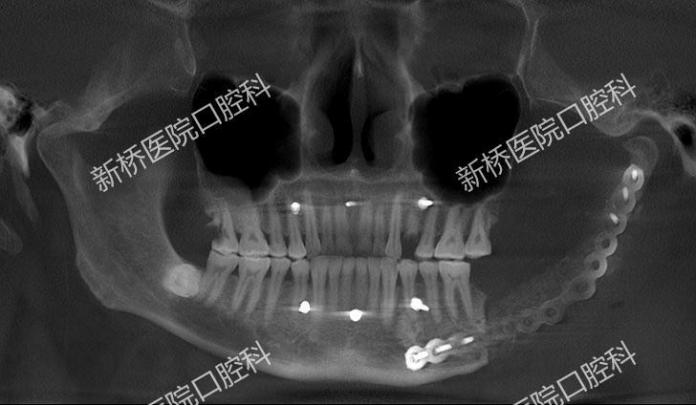

诱导膜技术修复颌骨缺损

骨水泥主要由聚甲基丙烯酸甲酯(PMMA)粉末和液态甲基丙烯酸甲酯(MMA)单体组成。骨水泥具有良好的生物相容性、化学稳定性和较高的机械强度,且在固化过程中放热较少,对周围组织影响较小。

多是在骨科当中应用,用于处理骨折、关节病变或骨质疏松等问题。它的主要原理就是在植入之后,能形成一层诱导膜,这层膜内部可以产生成骨微环境,诱导成骨,膜内填入骨松质后就可以在它的诱导下形成新骨。因此骨水泥主要有填充缺损、支撑以及诱导成骨的作用。